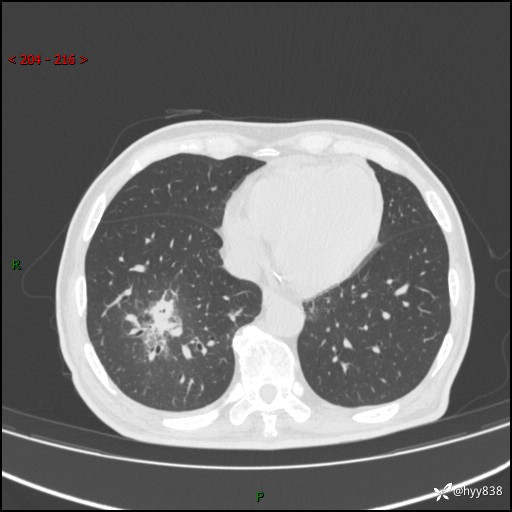

66岁/男,确诊髓系白血病5月,乏力伴气促半月。孤立结节,“晕”的厉害---结果公布~

【患者信息】:66岁/男

【主诉】:确诊髓系白血病5月余,乏力纳差伴气促半月

【现病史及既往史】:患者5月前无明显诱因出现牙龈出血,未重视,2024.5.10社区体检查血常规发现全血细胞减少,后自觉活动后心慌气促,无发热、头痛、咳嗽咳痰、胸痛等,为进一步诊治来我院,门诊以“全血细胞减少”收入,入院后完善相关辅检入院后确诊急性髓系白血病。于2024.06.11给予阿扎胞苷+维奈克拉化疗,给予输血、升白细胞、抗过敏、止血治疗,化疗后粒细胞缺乏,转入层流病房,出现发热,予以抗感染(头孢唑肟、莫西沙星、美罗培南)、抗真菌(卡泊芬净、氟康唑)、利尿、调脂、利胆、护心、护胃、调节免疫(羟氯喹、白芍总苷)、通便、调节胃肠道菌群、营养支持等对症治疗,出院时患者牙龈出血、咳嗽咳痰、腹胀、便秘等不适较前好转,复查血常规提示白细胞计数升高,要求出院,建议继续住院观察,但患者仍要求出院,予以办理。2024-08-06到我院规律化疗,2024-08-08给予阿扎胞苷+维奈克拉化疗,给予输血、升白细胞、抗过敏、止血治疗,化疗后粒细胞缺乏,转入层流病房,出现发热,予以护心、护胃 、营养支持等对症治疗,好转后出院。院外自行停用维纳克拉。半月前患者无明显诱因出现乏力、纳差、活动后气促,无心慌、胸闷,无咳嗽、咳痰,无畏寒、发热等不适,现患者为求进一步诊治来我院,门诊以“急性髓系白血病”收入院。 发病以来,患者精神、饮食欠佳,睡眠一般,大小便如常,体力明显下降,体重无明显减轻。

【检查】:胸部CT平扫